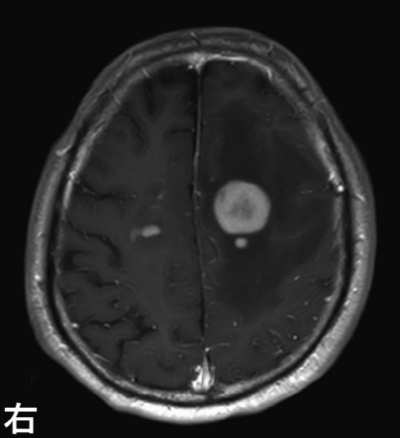

頭部造影MRI及び定位的脳生検術によって左前頭葉病変から採取した組織の H-E 染色標本と抗CD20抗体による免疫組織染色標本とを示す。FDG-PETでは脳以外に異常集積を認めない。